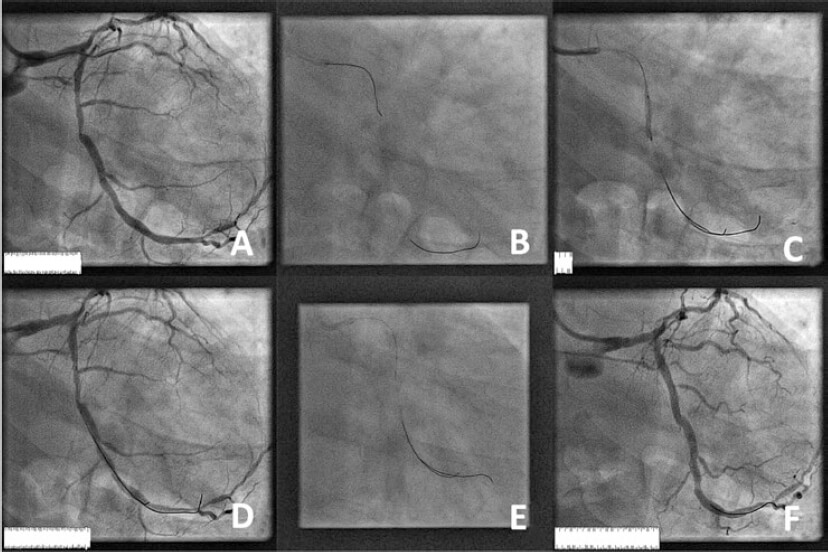

Varón hipertenso y exfumador de 55 años hospitalizado con signos de dolor torácico típico, bloqueo de rama izquierda y niveles normales de troponina. La angiografía reveló enfermedad coronaria de 2 vasos, circunfleja izquierda y coronaria derecha. Esta última se trató con un stent y la circunfleja izquierda mediante intervención guiada por el índice diastólico instantáneo sin ondas (iFR). Después se empleó una segunda guía convencional para dar estabilidad. La figura 1A muestra la angiografía inicial (vídeo 1 del material adicional), la ecualización de las presiones proximal y distal (figura 1B y figura 2A), la angioplastia simple con balón, la medición del gradiente de presión de enclavamiento mediante el iFR (figura 1C y figura 2D), el resultado angiográfico después de la angioplastia con balón (figura 1D), la medición del iFR después de la angioplastia con balón (figura 1E y figura 2E,F) y el resultado final (figura 1F, figura 2G,H y vídeo 1 del material adicional).

Figura 1.

La figura 2A muestra la ecualización, un iFR positivo después de la lesión (figura 2B), un cambio brusco del iFR durante la retirada que sugiere estenosis focal (figura 2C), el iFR durante el inflado del balón sin flujo anterógrado (gradiente de presión de enclavamiento según iFR) (figura 2D), el iFR 1 minuto después de la angioplastia (figura 2E), 4 minutos después sin maniobras ni fármacos (figura 2F), el iFR final y el iFR en retirada, respectivamente, después de implantar el stent (figura 2G,H).